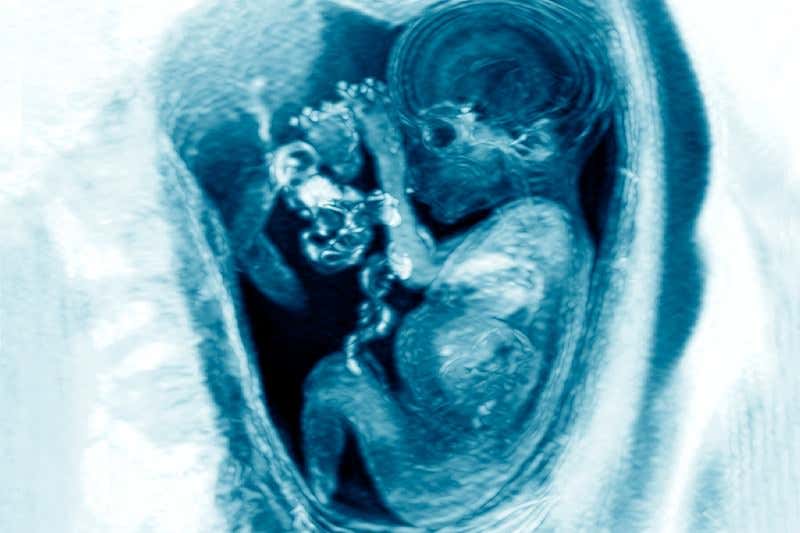

(Image: Du Cane Medical Imaging ltd/Science Photo Library)